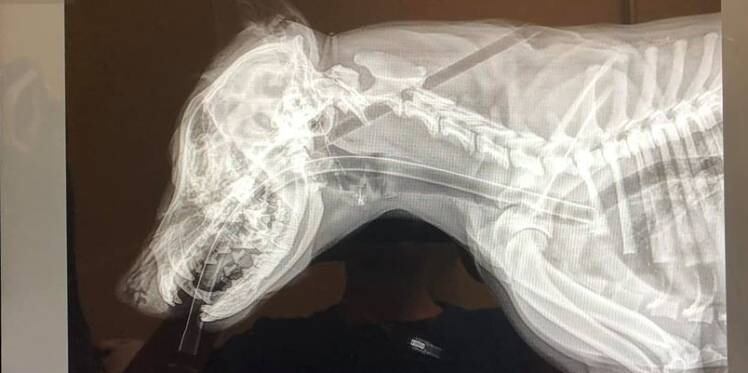

Las imágenes son verdaderamente impactantes y terribles. Una perrita de sólo 5 meses con una flecha clavada en la cabeza y que sale en el lomo.

De inmediato la llevaron a un centro de rehabilitación animal y ahí procedieron a salvarle la vida. Ahí la estabilizaron, le quitaron la flecha y afortunadamente sus signos vitales estaban bastante bien.

Acá puedes ver las imágenes, pero te advertimos, son muy fuertes.